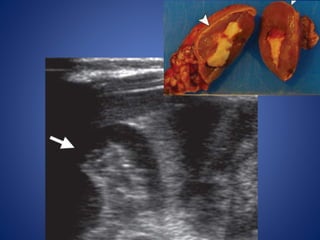

Testicular adrenal rest tumors in adrenogenital syndrome are

very common in boys with CAH.

These tumors are small, generally multiple, and often bilateral.

The involved testis may be enlarged, but its contour is not

distorted. The masses are eccentric and commonly surround the

mediastinum testis.

Their appearance at US is variable and depends on size.

Smaller lesions (<2 cm) appear hypoechoic compared with the adjacent

testicle, whereas larger lesions appear hyperechoic with posterior acoustic

shadowing.

At color Doppler imaging, vessels may be seen coursing through the lesion

without being deviated by it.

• #66 US image shows a small, well-circumscribed mass (arrowheads) with mixed echogenicity and some posterior acoustic shadowing